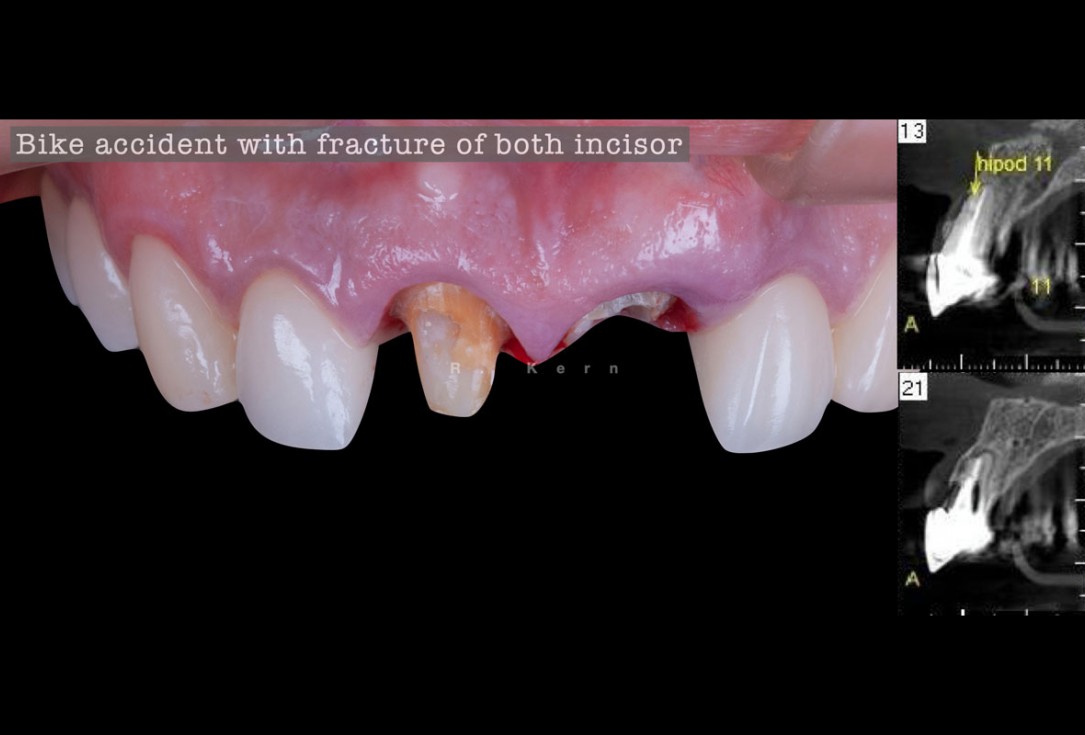

01/12 - Initial situation with fractured central incisors

Immediate implant placement and periimplant bone augmentation using cerabone® - Dr. R. Kern